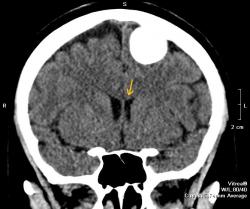

Полностью обызвествленная менингиома теменной области (красная стрелка). В прилегающей кости узурация (зеленые стрелки) и небольшой гиперостоз в виде клюва (голубая стрелка). Небольшой масс-эффект - крыша левого бокового желудочка поддавлена (желтая стрелка), субарахноидальные щели слева немного уже, чем справа. Перифокального отека нет - признак доброкачественности образования. Отек при менингиоме может развиться при очень больших размерах образования или при малигнизации. Пациентка жалуется на головные боли. На снимках черепа ничего необычного нет.

Спасибо. Очень наглядно. Особенно впечатляет отсутствие изменений на обычной рентгенограмме и такая картина, которую представили Вы. А как "судьба" пациентки?

Спасибо за пояснение. А "узурация" - это фактически локальный дефект кости?

Да, локальный дефект.

Опухоль доброкачественная, растет медленно годами, иногда десятилетиями. Но убирать ее надо, так как она уже вызывает сдавление головного мозга. Если ее убрать полность, а локализация, я думаю, позволяет, то рецидива не будет. Одно "но", опухоль богато васкуляризирована, во время удаления бывают кровопотери, кровоизлияния в ложе удаленной опухоли, что может привести к ишемии в окружающих тканях мозга, т. е. неврологический дефицит может оказаться, в результате этих осложнений, несколько большим, чем до операции. Но это не всегда происходит. Рецедивы происходят только при неполном удалении. Иногда менингиомы озлокачествляются и тогда рост их ускоряется, появляется перифокальный отек, участки распада, прорастание прилегающей кости.

Такие это какие, полностью обызвествленные? Такие не очень часто. Чаще с вкраплениями извести. Парасаггитальные часто, это одна из любимых локализаций. Нередко это случайные находки, так как единственная жалоба головные боли, а у кого голова не болит. Тянется это долго, нередко годами, очаговая неврологическая симптоматика не сразу развивается. КТ и МРТ у нас все еще не доступны для всех, страдающих головной болью.

Я прочитал, прошу прощения, что повторяюсь, но как-то не совсем понятно - "на рентгенограммах" черепа ничнго не было видно, даже с учетом того, что менингиома "полностью обызвествленная"?

Так было написано в описании. Снимки не видела, сама удивляюсь.